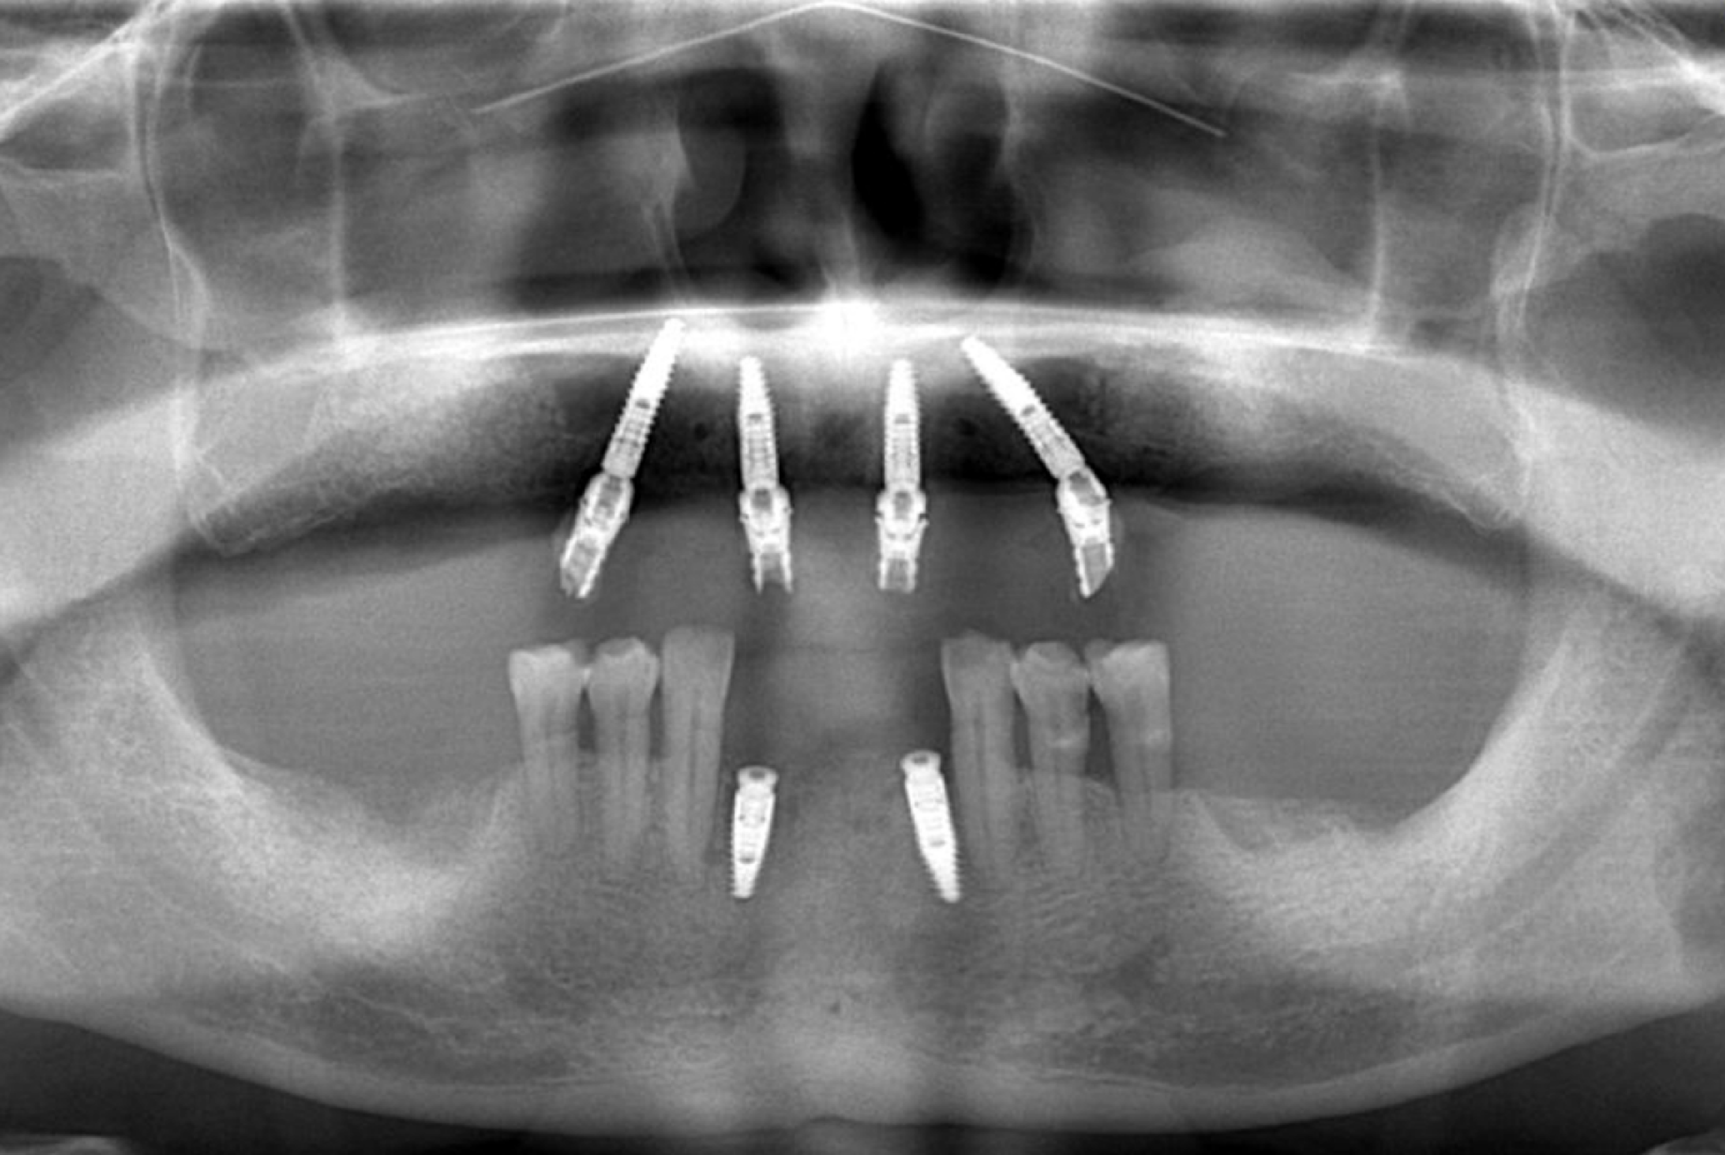

Fig. 4

Panoramic imaging of immediate restoration.